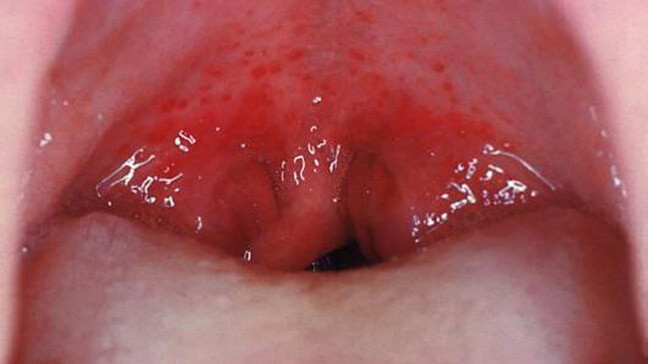

Bumps on the Back of the Tongue: Normal or Abnormal?

We don’t often think about our tongues, but they can actually be a marker of our overall health. The tongue’s appearance can change for many reasons, many of them not too serious. Have you ever noticed bumps on the back of your tongue? Often these bumps are caused by some type of oral infection. Find out what causes these bumps and when they are a cause for concern.

What Are Tongue Bumps?

The tongue is made up of muscles and the surface is covered with a mucous membrane. Typically, small bumps (also known as papillae) cover the surface of the back part of your tongue. Between the papillae are your taste buds that help you taste foods. Usually, these papillae are pretty unnoticeable. But sometimes, they become enlarged and can cause you pain. This can happen for many reasons.

What Are Common Causes of Bumps at the Back of the Tongue and How Can You Treat Them?

Some common reasons why you see large bumps at the back of your tongue include:

Oral thrush. If the inside of your mouth is red and you see white patches on your tongue and inner cheeks, you might have oral thrush. Wiping these patches off can leave red spots that bleed. The good news is that oral thrush is pretty harmless for most people and can be cured with antifungal medicine. However, oral thrush can be more serious for people with lower immunity, such as people experiencing cancer treatment or HIV/AIDS.

Leukoplakia. The primary symptom of this condition is thickened, white patches on your tongue, gums, bottom of the mouth, and the insides of your cheeks. They can’t be scraped off. Chronic irritation from tobacco is often the cause. While leukoplakia patches are usually noncancerous, some do show early signs of cancer. So, if you’re noticing these patches, it’s best to consult with your dentist or doctor as soon as possible.

Cold sores. Also known as fever blisters, these sores are caused by the herpes simplex virus (HSV) and can appear on your lips, inside your cheeks, or on your tongue. They begin as a fluid-filled blister that ruptures after a day or two before starting to heal. The sores usually last around 8-10 days and are highly contagious. Avoid oral contact — like kissing — during this time, and do not share utensils, lip balms, or other items that have touched your mouth. Cold sores usually heal on their own, and though you might be able to speed up the process with antiviral medications or creams, there is no way to get rid of HSV.

Scarlet fever. One of the symptoms of scarlet fever is a red and bumpy (“strawberry”) tongue. It’s usually accompanied by a very red, sore throat, high fever, red skin rash, and the skin in the creases of your underarm, elbow, and groin turning bright red. Scarlet fever most often occurs in children or adults who are in contact with children. Bacteria called group A strep causes this condition, and your doctor will usually prescribe antibiotics to help get rid of the bacteria.

Oral squamous papilloma. This is a benign mass that appears on the border of the tongue. They are often attributed to the human papillomavirus (HPV). According to a study in the International Journal of Scientific Reports, the best way to remove them is through surgery. They’re also unlikely to recur, except in immunocompromised patients.

Tongue cancer. Rarely, bumps on the tongue can be an indication of oral cancer. However, according to Cedars-Sinai, the lump is most likely to appear on the side of the tongue that touches the teeth. But the lump can appear on any portion of the tongue, and lumps on the base of the tongue are often hard to diagnose until they become larger. Early detection is critical here, so you must make an appointment with your doctor if you notice a lump of any size on your tongue. The lump will need to be biopsied, and your doctor will likely refer you to an oncologist.

If your notice tongue bumps at the back of your mouth, it’s normal to be worried. But the good news is that most bumps on your tongue aren’t a cause for too much concern. That said, if your bumps are large, last for several weeks, or are exceptionally painful, don’t hesitate to get them checked. Your doctor or dentist can help you feel comfortable again in no time!